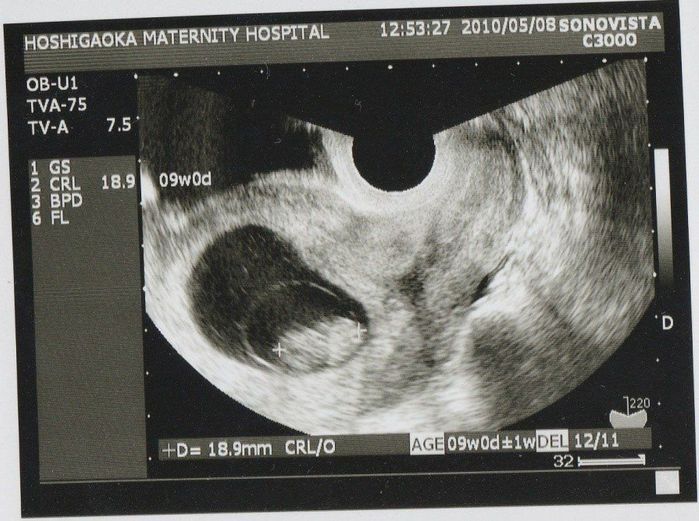

妊娠9週目のエコー写真

この写真から、胎嚢の中の我が子が二頭身になっていることがわかります。赤ちゃんの大きさは18.9mm。ちょうど枝豆一粒くらいの大きさですが、この時期は胎芽から胎児へ移行する時期のようです。それほど体調に変化もなく、「本当に自分のおなかに赤ちゃんがいるのか」と不思議な気持ちでした。